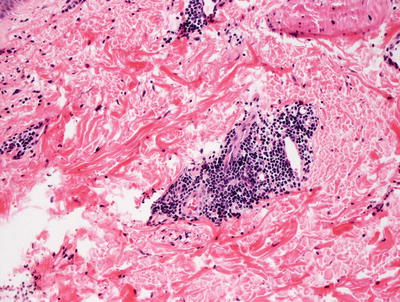

Fig. 5.5

Histologic findings in pigmented purpura are those of a superficial perivascular lymphocytic infiltrate with minimal epidermal involvement. Hemosiderin-laden macrophages are readily apparent even at low magnification